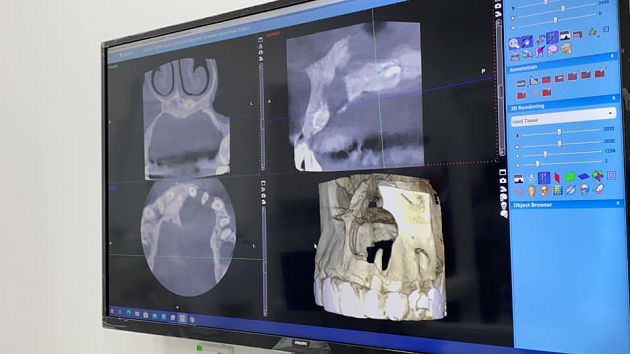

許佳麟也大方分享自己手術和牙齦的照片,從X光的照片中,可以看見她的牙齦確實是被腐蝕了一個大洞,可怕的樣子讓許多粉絲嚇傻!不過許佳麟也激勵自己,希望接下來可以一切順利,也表示日子還是要過,態度相當樂觀。